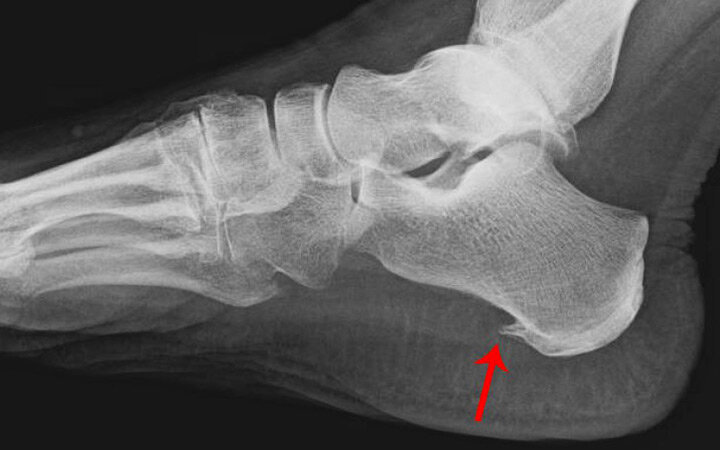

В месте её прикрепления к пяточной кости начинается воспалительный процесс. Он затрагивает поверхностные слои костной ткани и организм включает защитный механизм: начинает укреплять фасцию в месте повреждения за счет скопления ионов кальция. Связка сначала утолщается, становится менее эластичной, а затем часть её окостеневает. Так и образуется нарост на пяточной кости (остеофит) - шпора. Ортопеды различают два вида пяточной шпоры:

- подошвенная: костный отросток формируется со стороны подошвы;

- ахиллова (задняя): остеофит разрастается на задней поверхности пяточной кости в месте крепления ахиллова сухожилия (редкая форма).